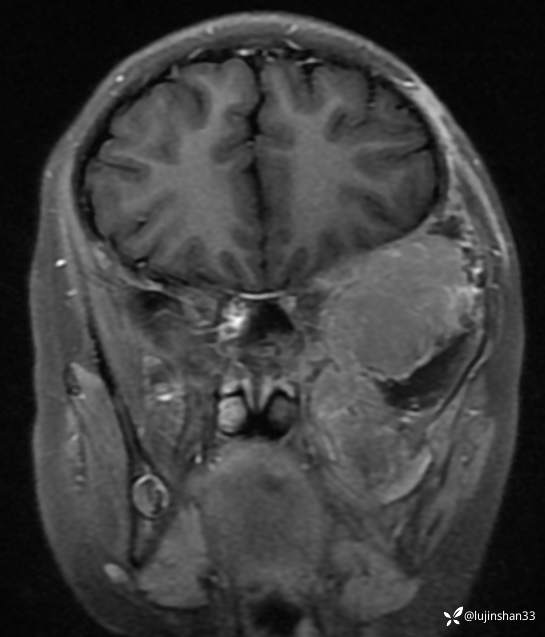

临床诊断:颅中窝、颞下窝小圆细胞恶性肿瘤

术后MRI:2022年2月考虑复发

小圆细胞恶性肿瘤术后放化疗效果如何?